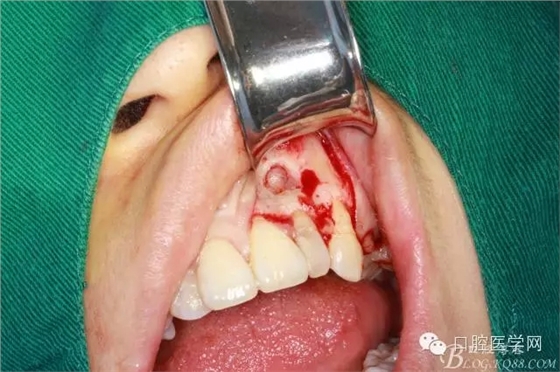

繼續(xù)去骨暴露牙根

牙根露出3mm左右因為根切長度

沖洗干凈開窗處

根切后可見開窗處清理干凈

刮出囊腫及牙根2.5MM